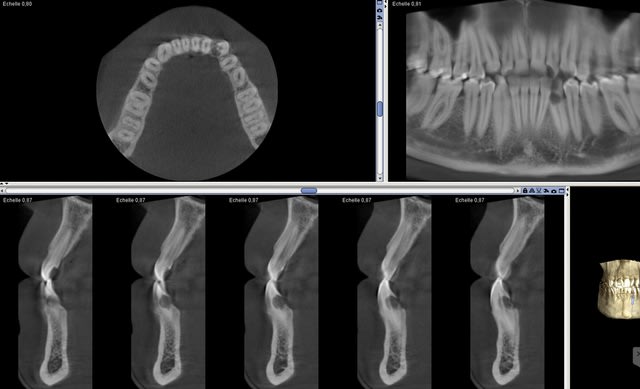

Un cône beam à 5 ça passe quand même mieux que tout seul!!!

> Un cône beam à 5 ça passe quand même mieux que tout seul!!!

Un cone beam ca se paye presque tout seul, tout seul.

Un capteur rvg ca se paie tout seul (minimum 4 radios par patient et maxi 14 en fonction de la situation clinique) et ca paie meme tout un cabinet en plus. J'ai des doutes quand au cone beam dont les indications HAS sont limitées. . -))))

Pour les deux j'ai coté un cbct tarif sécu.. Je dois en faire 4-5 / mois, plus une vingtaine de panos. Leasing payé.

Pas si limitées que ça quand tu les connais

Pardon , Illimitées en NPC. -))))